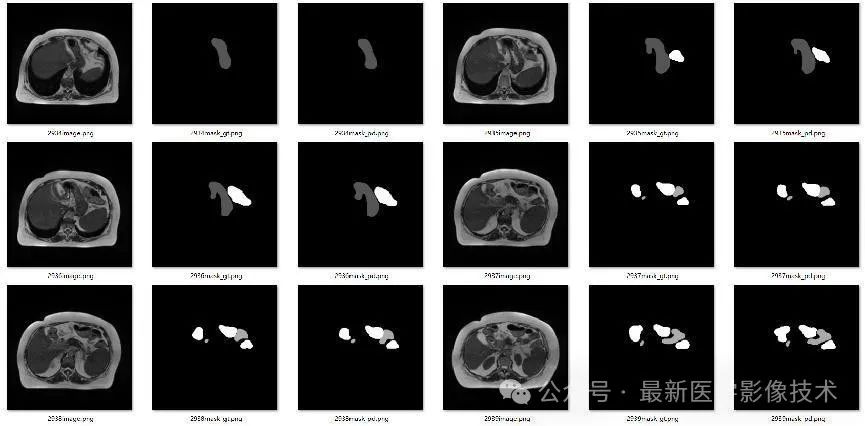

4、验证集部分分割结果